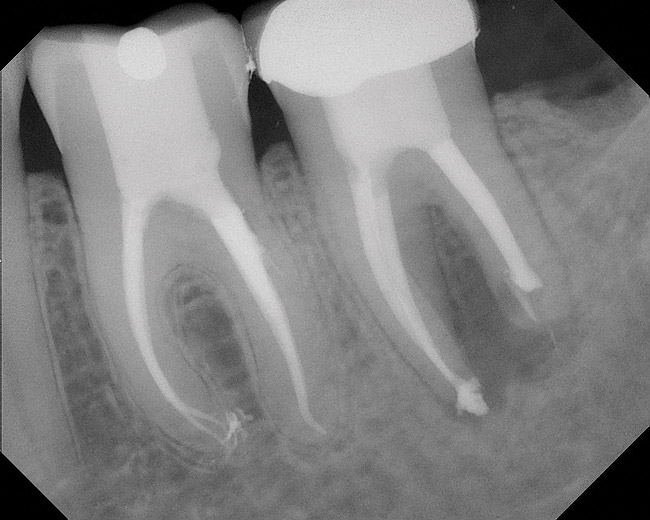

As mentioned, all risk factors associated with both root canal and implant therapy must be carefully considered. Comprehensive clinical and radiographic assessments are necessary to evaluate the patient's risk factors associated with his or her particular case (Figure 1, Figure 2 and Figure 3). The primary risk factors for implants can include smoking, bone quality, and systemic health. For endodontic therapy the primary risk factors are related to the anatomic root complexity, failed root canal treatment with significant technical defects manifested as iatrogenic events, less-than-optimal periodontal status of the tooth (due to a subsequent risk of vertical fracture), and a clinician's lack of experience with regard to the case's complexity. A strong correlation exists between failed root canal treatment and a lack of coronal seal after treatment. This is highly relevant in treatment planning. Often, endodontically treated teeth fail not because they were treated inappropriately and need extraction, but rather, because they have been left unsealed and assaulted by bacteria after the endodontic therapy, causing subsequent long-term clinical failure (Figure 4 and Figure 5).

While not elaborated on here, it is noteworthy that there are a number of additional treatments for resorption that have been suggested in the literature, including calcitonin,27 Emdogain,24,28 and Alendronate (third-generation bisphosphonate in treating EIRR)29 (Figure 6, Figure 7, Figure 8, Figure 9, Figure 10, Figure 11, Figure 12, Figure 13, Figure 14 and Figure 15).